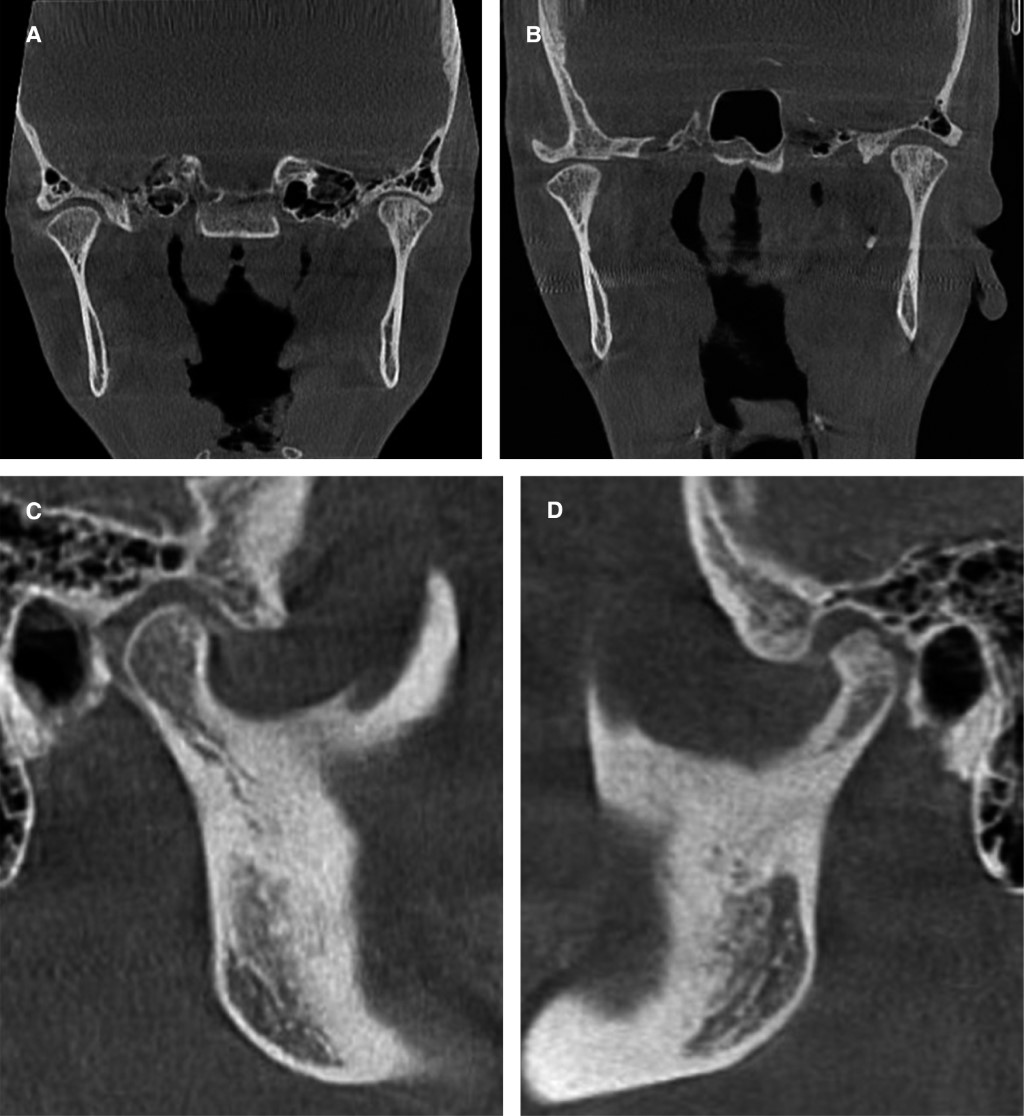

Entre las consideraciones que debemos tener en cuanto a las ATM, en primer lugar hay que evaluar el estatus en el cual se encuentran previo a la cirugía, particularmente en los casos en que se disminuirá la inclinación del plano oclusal. El o los movimientos que se lleven a cabo para reubicar el plano oclusal siempre serán sin generar sobrecarga por parte de los músculos sobre articulaciones, tejido blando y estructuras dentoalveolares para que tengan la oportunidad de readaptarse (Figura 6).11,22-24

Opdebeeck y colaboradores25 establecieron las diferencias morfométricas y anatómicas mediante cefalometrías en pacientes con síndrome de cara larga y cara corta. La principal diferencia morfológica se asocia con la rotación de la mandíbula, en el primer síndrome es hacia abajo y atrás (sentido horario); en cambio, en pacientes con síndrome de cara corta la mandíbula rota con dirección anterior y superior (sentido antihorario), lo que representa cambios en la posición condilar debido a la rotación mandibular, y en otras estructuras anatómicas que cambian de posición como el hueso hioides e incluso la lengua.

El reconocimiento del plano oclusal parece ser sencillo, pero cuando el clínico se enfrenta a alteraciones de curvaturas excesivas, mordidas abiertas o profundas o severa maloclusión, es complicado determinar el plano oclusal. Reyneke sugiere trabajar con el uso de dos diferentes planos oclusales, el oclusal superior y el oclusal inferior, los cuales son totalmente aplicables a la planificación quirúrgica.19,24,26-28